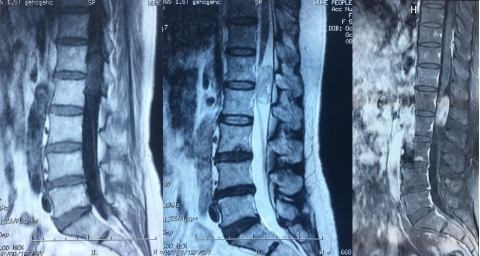

3)硬脊膜外肿瘤

肿瘤位于硬脊膜外,类似于电缆的绝缘层与保护壳之间的位置。最常见的类型是转移性肿瘤(图8),但也可能出现如海绵状血管瘤或脂肪血管瘤等情况。这类肿瘤通常发展较快,病程相对较短。在早期阶段,患者可能会出现根性疼痛,并可能迅速进展至瘫痪;而感觉障碍(如麻木、感觉异常)可能出现并随病情进展加重。病变区域有时会有明显的压痛感。通过影像学检查,可以观察到椎体骨质受损以及椎旁软组织的变化。

图8.上胸段硬膜外转移瘤MRI图像

5)转移性肿瘤

这类肿瘤可能是由于身体其他部位的恶性肿瘤通过动脉或静脉途径转移而来(多数位于硬脊膜外),也可能是中枢神经系统其他部位的恶性肿瘤通过脑脊液循环扩散所致(多见于髓外硬脊膜下或软脊膜下),常见于中年及以上人群。病情发展通常较快,患者可能会出现肌肉松弛无力的瘫痪以及较为严重的括约肌功能障碍,有时还伴随椎体破坏。